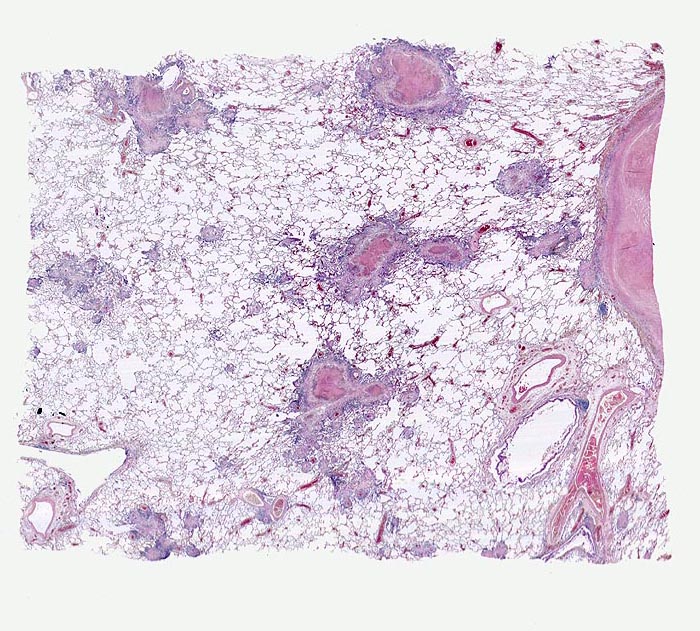

AP/ Lungentuberkulose

Lungentuberkulose

Das morphologische Bild ist äusserst variabel. Je nach Abwehrlage, Art und Geschwindigkeit der Ausbreitung entstehen unterschiedlich grosse, teils geschichtete Herde mit unterschiedlichem Grad an Epitheloidzellreaktion, zentraler Nekrose bzw. Vernarbung. Rein produktive Granulome ohne Nekrosen sind Zeichen guter Abwehrlage. Der Begriff Verkäsung bezieht sich auf den makroskopischen Aspekt von Nekrosen, der an Frischkäse erinnert. Exsudative nekrotisierende Granulome entstehen bevorzugt bei schlechter Abwehrlage. In späteren Stadien der Lungentuberkulose unterscheidet man produktive Phthisen mit azinös nodösen Gruppen von bronchogen entstandenen gering verkäsenden Streuherden (Präparat), zirrhotische Phthisen mit gering verkäsenden stark vernarbenden Herden und exsudative Phthisen bei schlechter Abwehrlage. Bei letzterer steht die Verkäsung im Vordergrund. Die bakterienreichen Herde entstehen teils hämatogen, teils bronchogen. Verkäsende Herde sind Ausgangspunkt für die Kavernenbildung. Kavernen stellen die wichtigste Quelle für die bronchogene Streuung dar.

• Tuberkulöse Herde ausgehend von vollständig oder partiell entzündlich zerstörten Bronchiolen in unmittelbarer Nachbarschaft von Arterien.

• Granulome mit zentraler käsiger Nekrose mit Kerntrümmern umgeben von einem Epitheloidzellwall und einem äusseren blauen Saum von Lymphozyten.

• Schlanke spindelige Epitheloidzellen und einzelne Riesenzellen vom Langhanstyp mit peripher hufeisenförmig angeordneten Kernen.